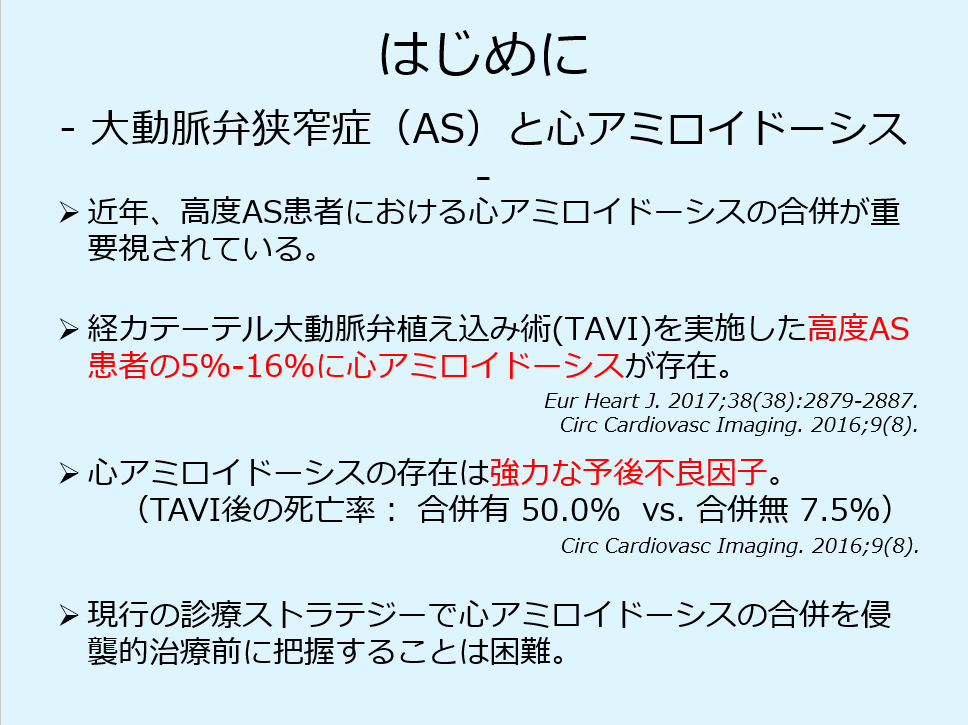

ASと心アミロイドーシスの関連性については、循環器領域で大変、トピックスとなっています。

TAVIを施行したsevere AS患者の5%−16%に心アミロイドーシスが存在していることが報告され、TAVIにおいて、心アミロイドーシスは強力な予後因子とされ、TAVI後の死亡率は50%と報告されています。